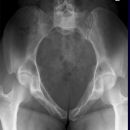

Becken a.p.

>90% aller Beckenringfrakturen lassen sich in der Übersichtsaufnahme, ggf. mit zusätzlicher Inlet und Outlet- Aufnahme (Bestimmung von Richtung und Ausmaß der Dislokation), diagnostizieren;

Beurteilungskriterien

- Symmetrie des Beckenskeletts, Position der Darmbeinkämme

- Weite und Symmetrie von Symphysenspalt (< 6mm) und ISF (< 4mm)

- Querfortsätze der unteren LWS, Kontur der Sakralforamina, ggf. CT

- Kontinuität der ilioischiadischen und iliopubischen Linie

- Azetabulumfraktur: vorderer und hinterer Pfannenrand, Pfannendachkontur, Köhlersche Tränenfigur, ggf. Zusatzaufnahmen (ap-Zielaufnahme, axiale, Ala- und Obturatoraufnahme), sowie CT

- Schenkelhalswinkel, Weite des Hüftgelenksspalt (4-5mm nach medial, 3-4mm nach kranial)

- Hüftluxation? Hüftkopf in der Beckenübersicht und in der axialen Aufnahme in der Pfanne zentriert?